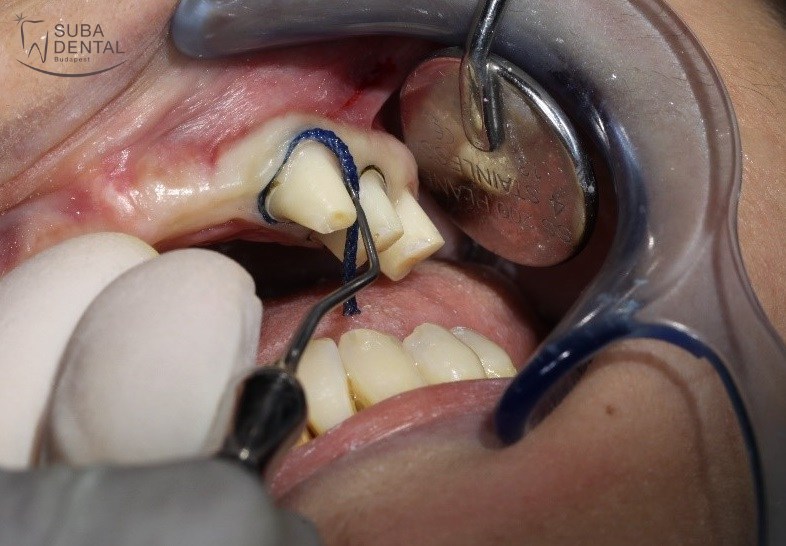

Szulkusztágító fonal behelyezése a fogak lecsiszolásánál. A fogtechnikus így pontosan látja a fog peremét és pontosan tudja elkészíteni a koronákat